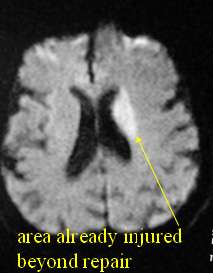

When there is damage to the brain by rupture of a vessel, it is called a hemorrhagic (bleeding) stroke. When it is caused by a blood clot or atherosclerotic narrowing leading to blockage of a blood vessel, then it is called an ischemic (lack of blood flow) stroke. A stroke is an injury to the brain that causes a permanent loss of function (Figure 2). Typical ischemic stroke symptoms are loss of sensation or strength, typically on one side (face, arm and/or leg), loss of vision, garbled speech or inability to understand speech, or loss of balance. If these symptoms are short lived (less than a few minutes), it is called a transient ischemic attack (TIA) in contrast to a stroke which results in permanent loss of function. A TIA is sometimes referred to as a mini stroke. But there is nothing trivial about it as the name may imply. Rather it is a warning sign for a possible large stroke forthcoming. The risk of subsequent stroke is 10 times higher after a TIA and in fact this is an opportunity to intervene, identify the cause of the TIA, treat the cause of the TIA and prevent a future stroke. Stroke and TIA are both emergencies requiring urgent evaluation, work up and treatment.